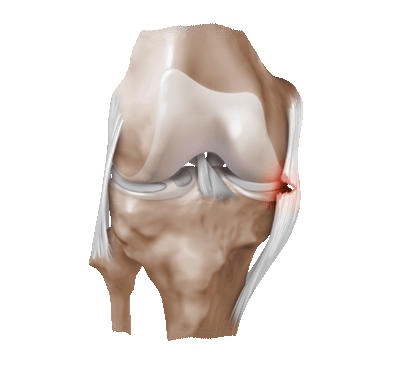

![]()

Частичный надрыв боковой связки коленного сустава.